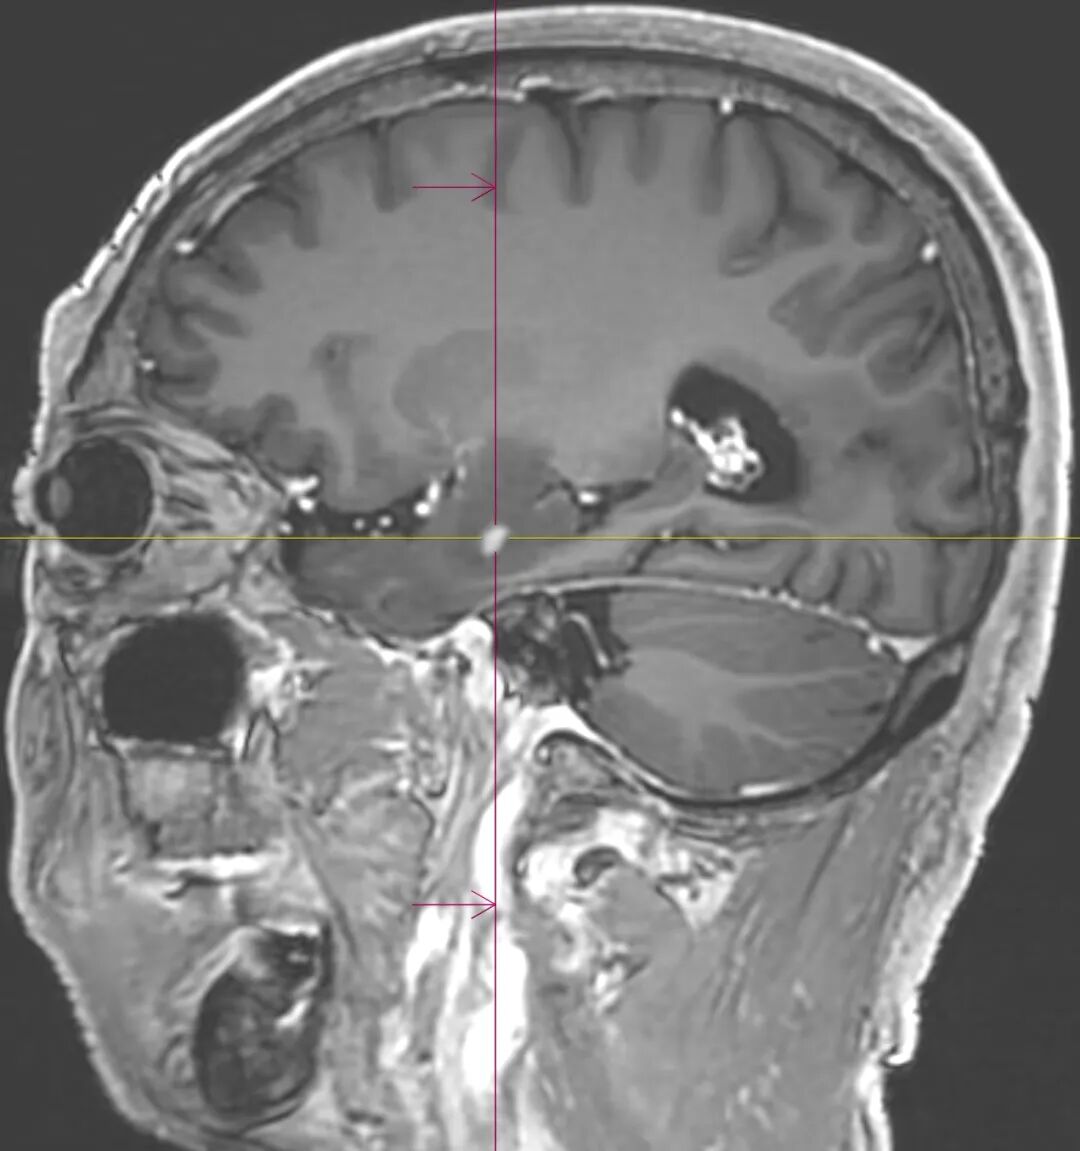

中大专家坐镇|玉溪中山医院开展3D磁共振扫描,精准找病灶,手术更安心

在现代医学影像技术的浪潮中,磁共振成像(MRI)以无辐射、高软组织分辨力、多参数成像的独特优势,成为疾病诊断的核心工具之一。而磁共振3D扫描技术,更以其立体成像的优势受到关注——它能为人体内部病变区域构建清晰的三维图像,让病灶细节无所遁形。如今,玉溪市中山医院医学影像科在中山大学附属第一医院派驻专家张朝晖教授的领衔下,已熟练开展多部位磁共振3D扫描技术,将这项前沿技术转化为精准诊断与治疗的“硬核支撑”...